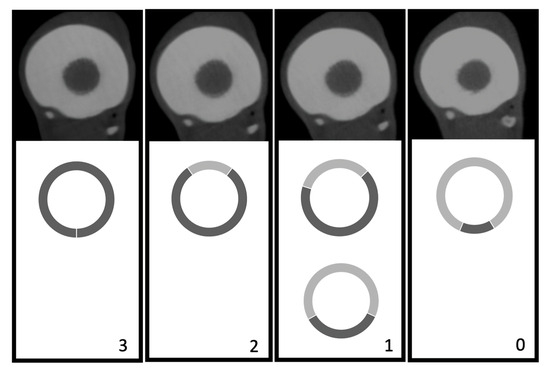

2.2.1. Visual Image Quality Assessment

| Variable | Rating |

|---|---|

| Distinctness of anatomical structure |

|

| |

| CT artifacts |